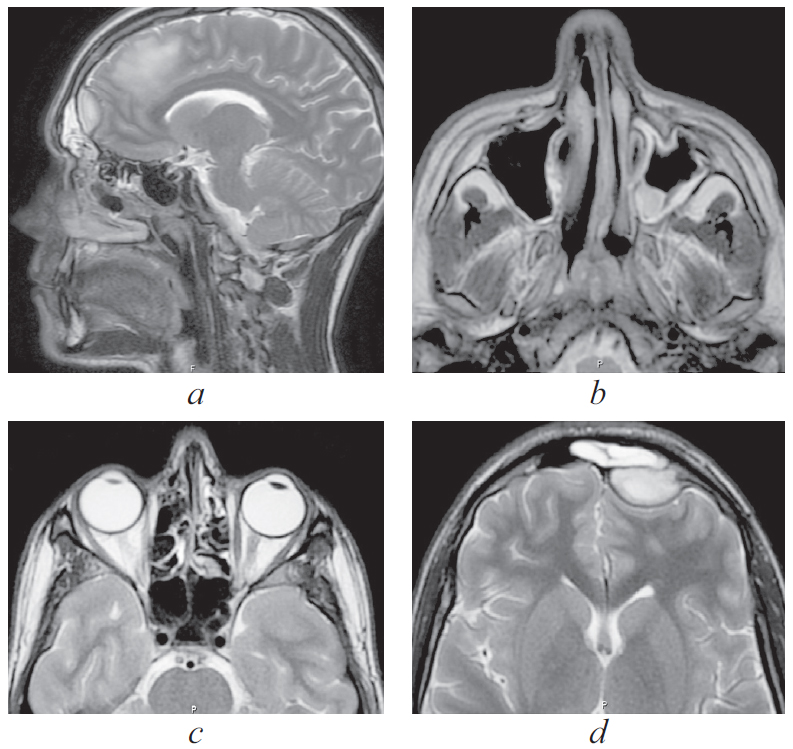

По результатам МРТ головного мозга от 16.06.2021 (рис. 2): МР-признаки подоболочечного скопления жидкости с высоким содержанием белка, воспалительных изменений оболочек в левой лобной области. Картина соответствует субдуральной эмпиеме.

Рис. 2. Магнитно-резонансная томография головного мозга от 16.06.2021: а — сагиттальная проекция в режиме Т2. Прослеживаются воспалительные изменения оболочек в левой лобной области. Картина соответствует субдуральной эмпиеме; b — аксиальная проекция в режиме Т2. Снижение пневматизации левой верхнечелюстной пазухи, пристеночный отек слизистой; c — аксиальная проекция в режиме Т2. Снижение пневматизации клеток решетчатого лабиринта; d — аксиальная проекция в режиме Т2. Воспалительные изменения оболочек в левой лобной области, субдуральная эмпиема

Fig. 2. Magnetic resonance imaging of the brain from 16.06.2021; a – sagittal projection in T2 mode. Inflammatory changes in the membranes in the left frontal region are traced. Picture consistent with subdural empyema; b – axial projection in T2 mode. Decreased pneumatization of the left maxillary sinus, parietal edema; c – axial projection in T2 mode. Decreased pneumatization of cells of the ethmoid labyrinth; d – axial projection in T2 mode. Inflammatory changes in the membranes in the left frontal region, subdural empyema